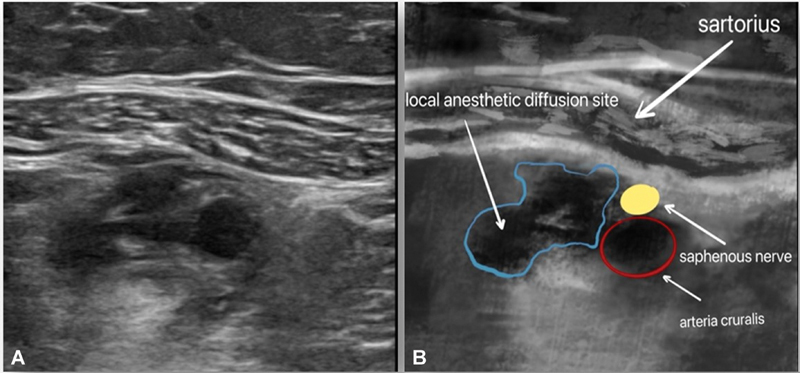

我们的目的是比较腘动脉与膝关节后囊间间歇多次浸润(IPACK)联合内收管阻滞(ACB)和单独间歇ACB对屈曲挛缩性膝关节炎患者行全膝关节置换术(TKA)的镇痛效果。将46例选择性单侧TKA患者分为间歇多次IPACK联合ACB组(IA组)和间歇多次ACB组(A组),每组ACB用0.375%罗哌卡因20 mL, IA组IPACK用0.25%罗哌卡因20 mL。术后第1天[POD1]和术后第2天[POD2]上午7:30 ~ 8:30采用间歇性多重神经阻滞进行术后镇痛(IPACK阻滞联合ACB组为IA组,ACB组为A组)。评估的主要结果是休息时疼痛、运动诱发疼痛(MEP)和POD1和POD2的活动范围(ROM)。次要结局包括阿片类药物消耗、首次下床时间、下床距离和术后并发症。我们观察到,与A组相比,IA组MEP降低,ROM变宽,行走距离变长,阿片类药物消耗减少。其他结果要么组间相似,要么临床差异不显著。我们得出结论,在屈曲挛缩性膝关节炎患者行TKA时,多次间歇性IPACK联合ACB治疗比单独多次间歇性ACB治疗提供更好的镇痛效果。

We aimed to compare the analgesic effects of intermittent multiple infiltrations between the popliteal artery and capsule of the posterior knee (IPACK) combined with adductor canal block (ACB) and intermittent ACB alone in patients with flexion contracture knee arthritis undergoing total knee arthroplasty (TKA). Forty-six patients who underwent elective unilateral TKA were divided into two groups (n = 23 each): intermittent multiple IPACK combined with ACB (group IA) and intermittent multiple ACB (group A). ACB was performed with 20 mL of 0.375% ropivacaine in each group and IPACK with 20 mL of 0.25% ropivacaine in group IA. Intermittent multiple nerve blocks were used for postoperative analgesia (IPACK block combined with ACB in group IA and ACB in group A between 7:30 and 8:30 a.m. on postoperative day 1 [POD1] and postoperative day 2 [POD2]). Primary outcomes assessed were pain at rest, motion-evoked pain (MEP), and range of motion (ROM) on POD1 and POD2. Secondary outcomes included opioid consumption, first ambulation time, ambulation distance, and postoperative complications. We observed that compared with group A, MEP decreased, ROM became wider, ambulation distance was longer, and opioid consumption decreased in group IA. Other outcomes were either similar between the groups or showed clinically insignificant differences. We conclude that multiple intermittent IPACK therapy combined with ACB provides superior analgesia than multiple intermittent ACB therapy alone in patients with flexion contracture knee arthritis undergoing TKA.